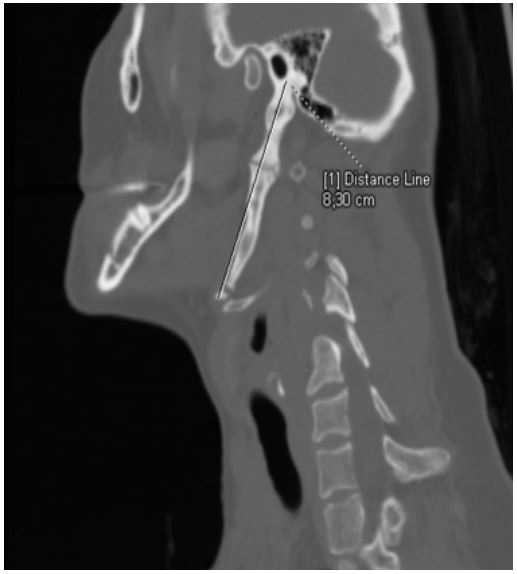

Computed tomography of the neck without contrast administration showed bilateral elongated styloid processes. On the left side the overal lenght of the styloid process was 8,3 cm. Aditionally within the left styloid process we observed two false joints, one of them in the down part, reposition the hyoid bone in caudal direction (Figure 3). Maximum width of the left styloid process was 1,3 cm and it was located at the level of upper false joint. Right styloid process was elongated insignificantly (3,65 cm) and didn’t cause pain or any other symptoms.

Figure 1: Multidetector computer tomography (MDTC) with 3D volumetric reconstructions (3D-VR) - left-sided sagittal view.

Figure 2: Multidetector computer tomography (MDTC) with multi-planar reconstructions (MPR) - left-sided sagittal view. Measurement of the overall length of left styloid process.